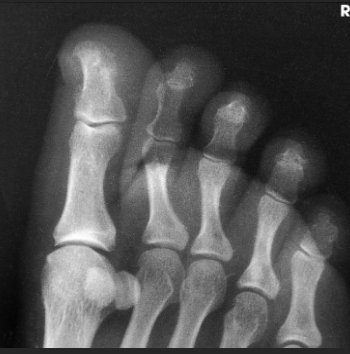

Name this projection.

AP oblique toes

State the degree and type of rotation used.

Medial rotation 30-45 degrees

Which aspect of the foot rests on the IR?

Medial aspect

Where does the CR enter?

Perpendicular to 3rd MTP joint

When radiographing the 1st-2nd toes, which oblique should be used?

Medial (rotate on medial/unaffected side)

When radiographing the 4th-5th toes, which oblique should be used?

Lateral (rotate on lateral/affected side)